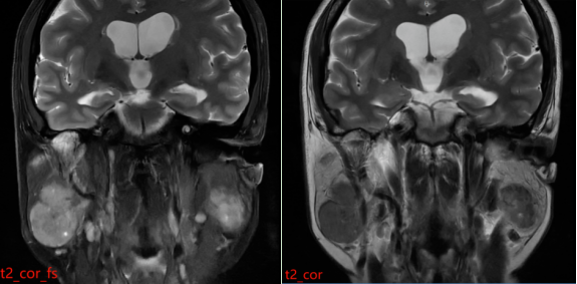

患者接受了磁共振(MR)检查,影像表现如下:

MR表现:双侧腮腺浅叶下极见结节状略混杂信号,T1以低信号为主、T2以 稍高信号为主,DWI呈稍高信号,ADC图呈稍低信号,边界清晰,增强扫描病变中等强化,强化较均匀,其内见点状无强化影。